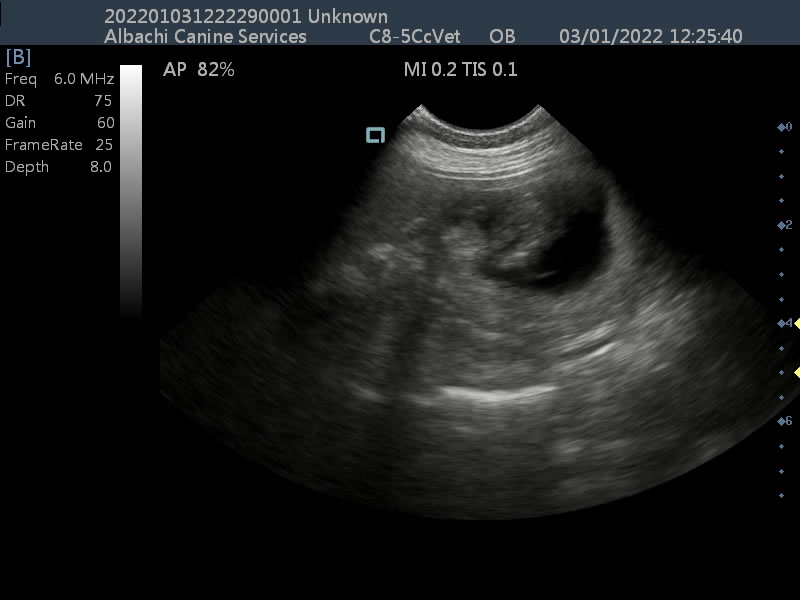

A late stage scan for Elsie the Pomeranian, showing development of pups. Videos and images show developed organs and heart beats.